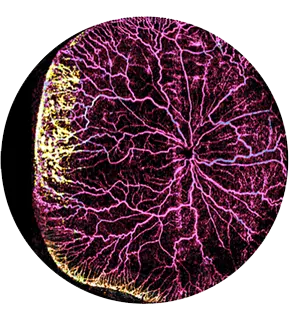

Our patented Scanning Laser Ophthalmoscope (SLO) camera is designed to capture high-quality, truly ultra-wide field images of eyes across all ages.